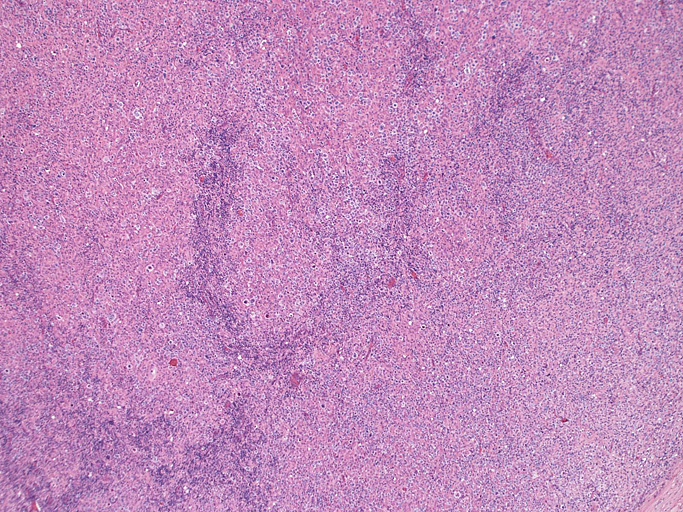

頸部リンパ節病理組織所見

ebvdlbcl01.jpg

直径17mmの腫大したリンパ節。被膜は軽度線維性肥厚を示す。リンパ節の基本構造は失われ不明瞭な結節様構造が集蔟しているように見える。

光顕および免疫染色所見

結節構造内では, 好酸性細胞質をもつ組織球の増生を背景に大型異型細胞が散在性または集蔟して増殖している。被膜下にも線維化組織内にbizzarreな大型細胞が認められる。リンパ球は小型リンパ球が大型異型細胞を含む組織球性の結節辺縁に存在する。大型細胞は, centroblastic cellが多く, その他 Hodgkin cell-like cell, RS細胞様巨細胞, 腎臓型の核をもった細胞, 多型核の細胞など多彩な形態を示す。異型核分裂像をふくむ核分裂像が多い。